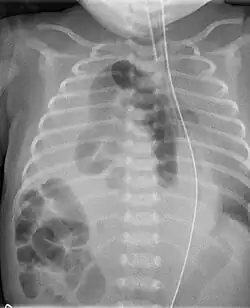

Angeborene rechtsseitige Zwerchfellhernie eines Neugeborenen im Thorax-Röntgenbild

Nach der Geburt fallen die Kinder durch Atemnot oder Kahnbauch auf, ein Röntgenbild des Brustkorbes zeigt dann, dass im Brustkorb außer Lunge und Herz noch weitere Organe liegen.